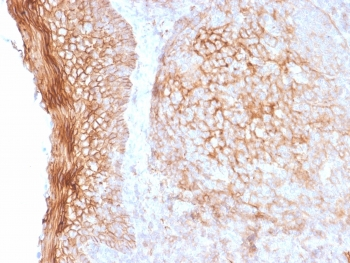

IHC staining of FFPE human tonsil tissue with CD73 antibody (clone NT5E/2545). HIER: boil tissue sections in pH9 10mM Tris with 1mM EDTA for 10-20 min and allow to cool before testing.

IHC staining of FFPE human tonsil tissue with CD73 antibody (clone NT5E/2545). HIER: boil tissue sections in pH9 10mM Tris with 1mM EDTA for 10-20 min and allow to cool before testing.